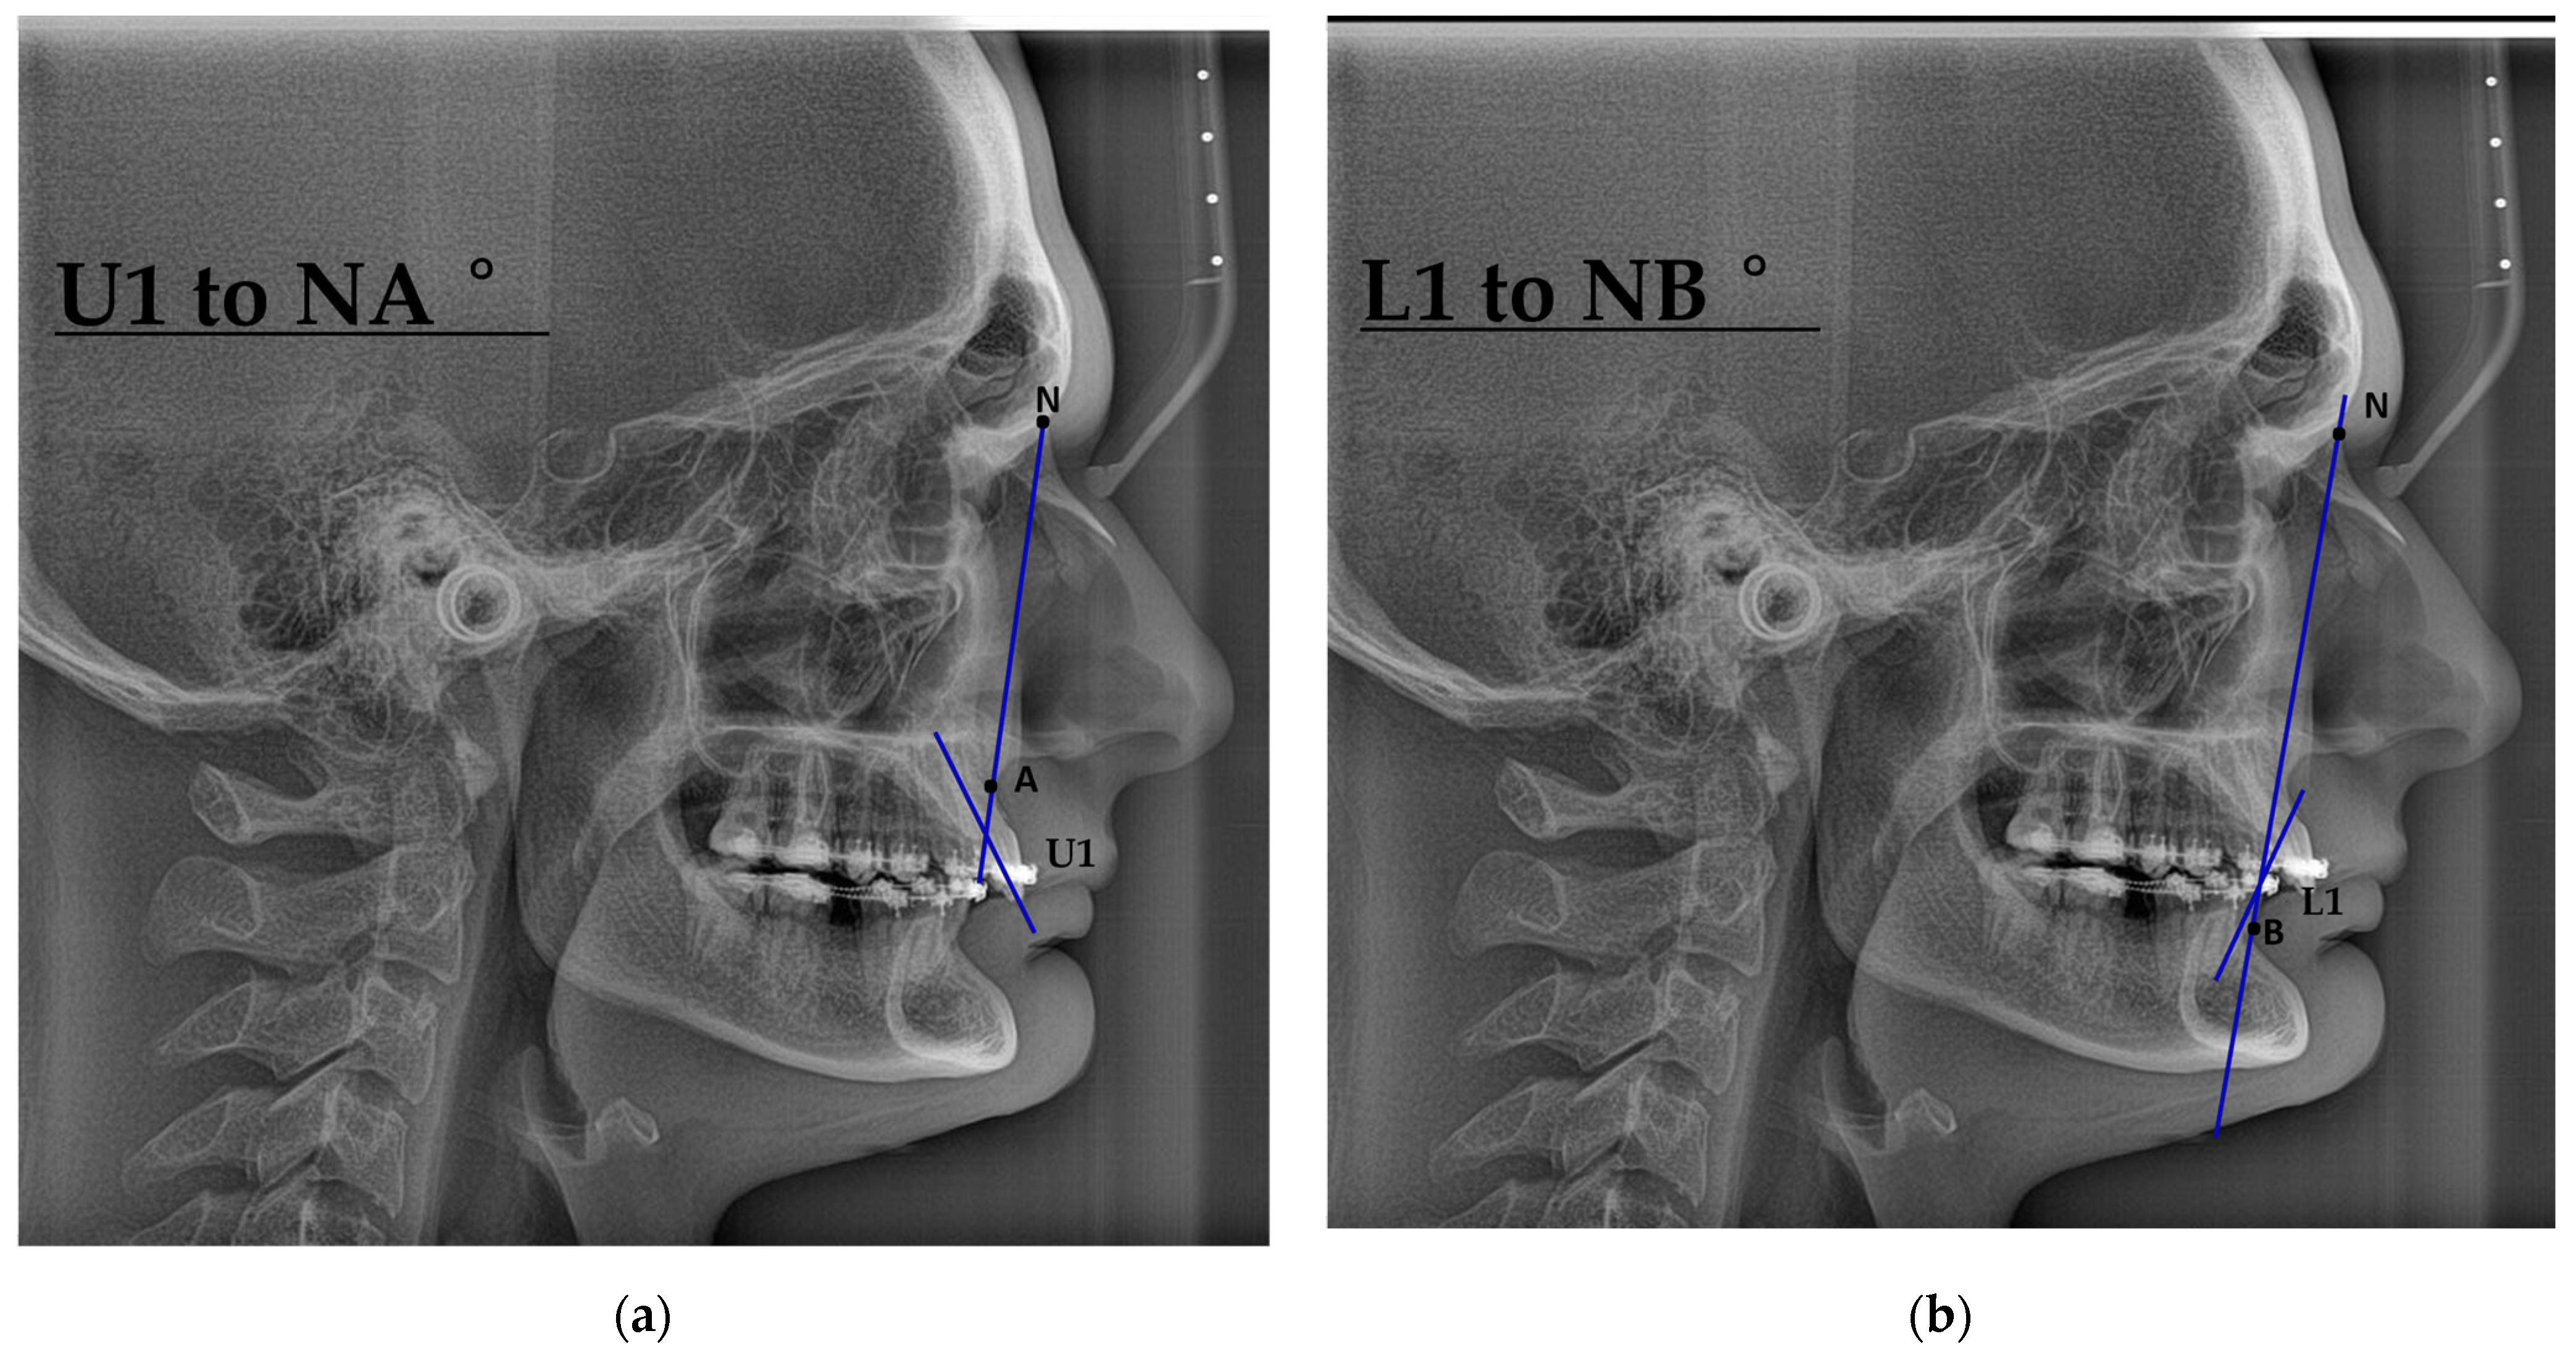

| Characteristic | Preoperative Median (IQR) | Postoperative Median (IQR) |

|---|---|---|

| Demographics | ||

| Age (years) | 28.0 (24.0, 33.0) | – |

| Sex, n (%) | Female: 11 (44%) Male: 14 (56%) | – |

| Skeletal parameters | ||

| SNA (°) | 83.6 (79.9, 84.9) | 86.3 (80.4, 89.0) |

| SNB (°) | 83.5 (76.8, 87.2) | 84.0 (81.0, 86.0) |

| ANB (°) | 0.9 (−4.9, 5.3) | 3.0 (−0.2, 4.5) |

| Pogonion to N-Perpendicular FH (mm) | 1.87 (−0.94, 2.31) | 1.4 (0.4, 2.6) |

| Dental parameters | ||

| U1–NA (°) | 26 (21, 28) | 22 (19, 29) |

| L1–NB (°) | 24 (17, 27) | 25 (19, 30) |

| Soft tissue parameters | ||

| Nasolabial angle (°) | 102 (92, 114) | 105 (91, 117) |

| Facial convexity (°) | 0 (−12, 7) | 2 (−6, 5) |

| Variable | Mean Difference | SE Difference | t | df | p-Value |

|---|---|---|---|---|---|

| SNA (°) | −3.123 | 1.24 | −2.511 | 24 | 0.019 |

| SNB (°) | −1.147 | 1.41 | −0.811 | 24 | 0.426 |

| ANB (°) | −1.980 | 1.00 | −1.977 | 24 | 0.060 |

| Pogonion to N-Perpendicular FH (mm) | −1.571 | 1.21 | −1.296 | 24 | 0.207 |

| U1–NA (°) | 0.465 | 1.87 | 0.249 | 24 | 0.806 |

| L1–NB (°) | −2.968 | 1.55 | −1.915 | 24 | 0.067 |

| Nasolabial angle (°) | −6.950 | 8.83 | −0.787 | 24 | 0.439 |

| Facial convexity (°) | −0.502 | 4.12 | −0.122 | 24 | 0.904 |